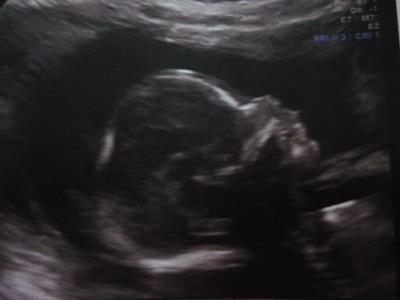

...Huhu Mädels, wir waren gerade bei der Feindiagnostik, und es ist alles alles super! :) Unser kleiner Junge ist total gut entwickelt alles in der Norm, ca 300gr schwer und 23cm groß. Hat wohl sehr lange Beine, hat der Papa ja auch (der kam mit 58cm auf dei Welt!) :) Und keine Lippen Kiefer Gaumen Spalte..das war meine größte Sorge da das ja bei uns in der Familie liegt! Anbei noch ein Bildchen von unserem Racker! :) Frohe Ostern wünsche ich Euch, lg

Bild zu Komme von der Feindiagnostik...+ Bildchen! - Forum für September - Mamis